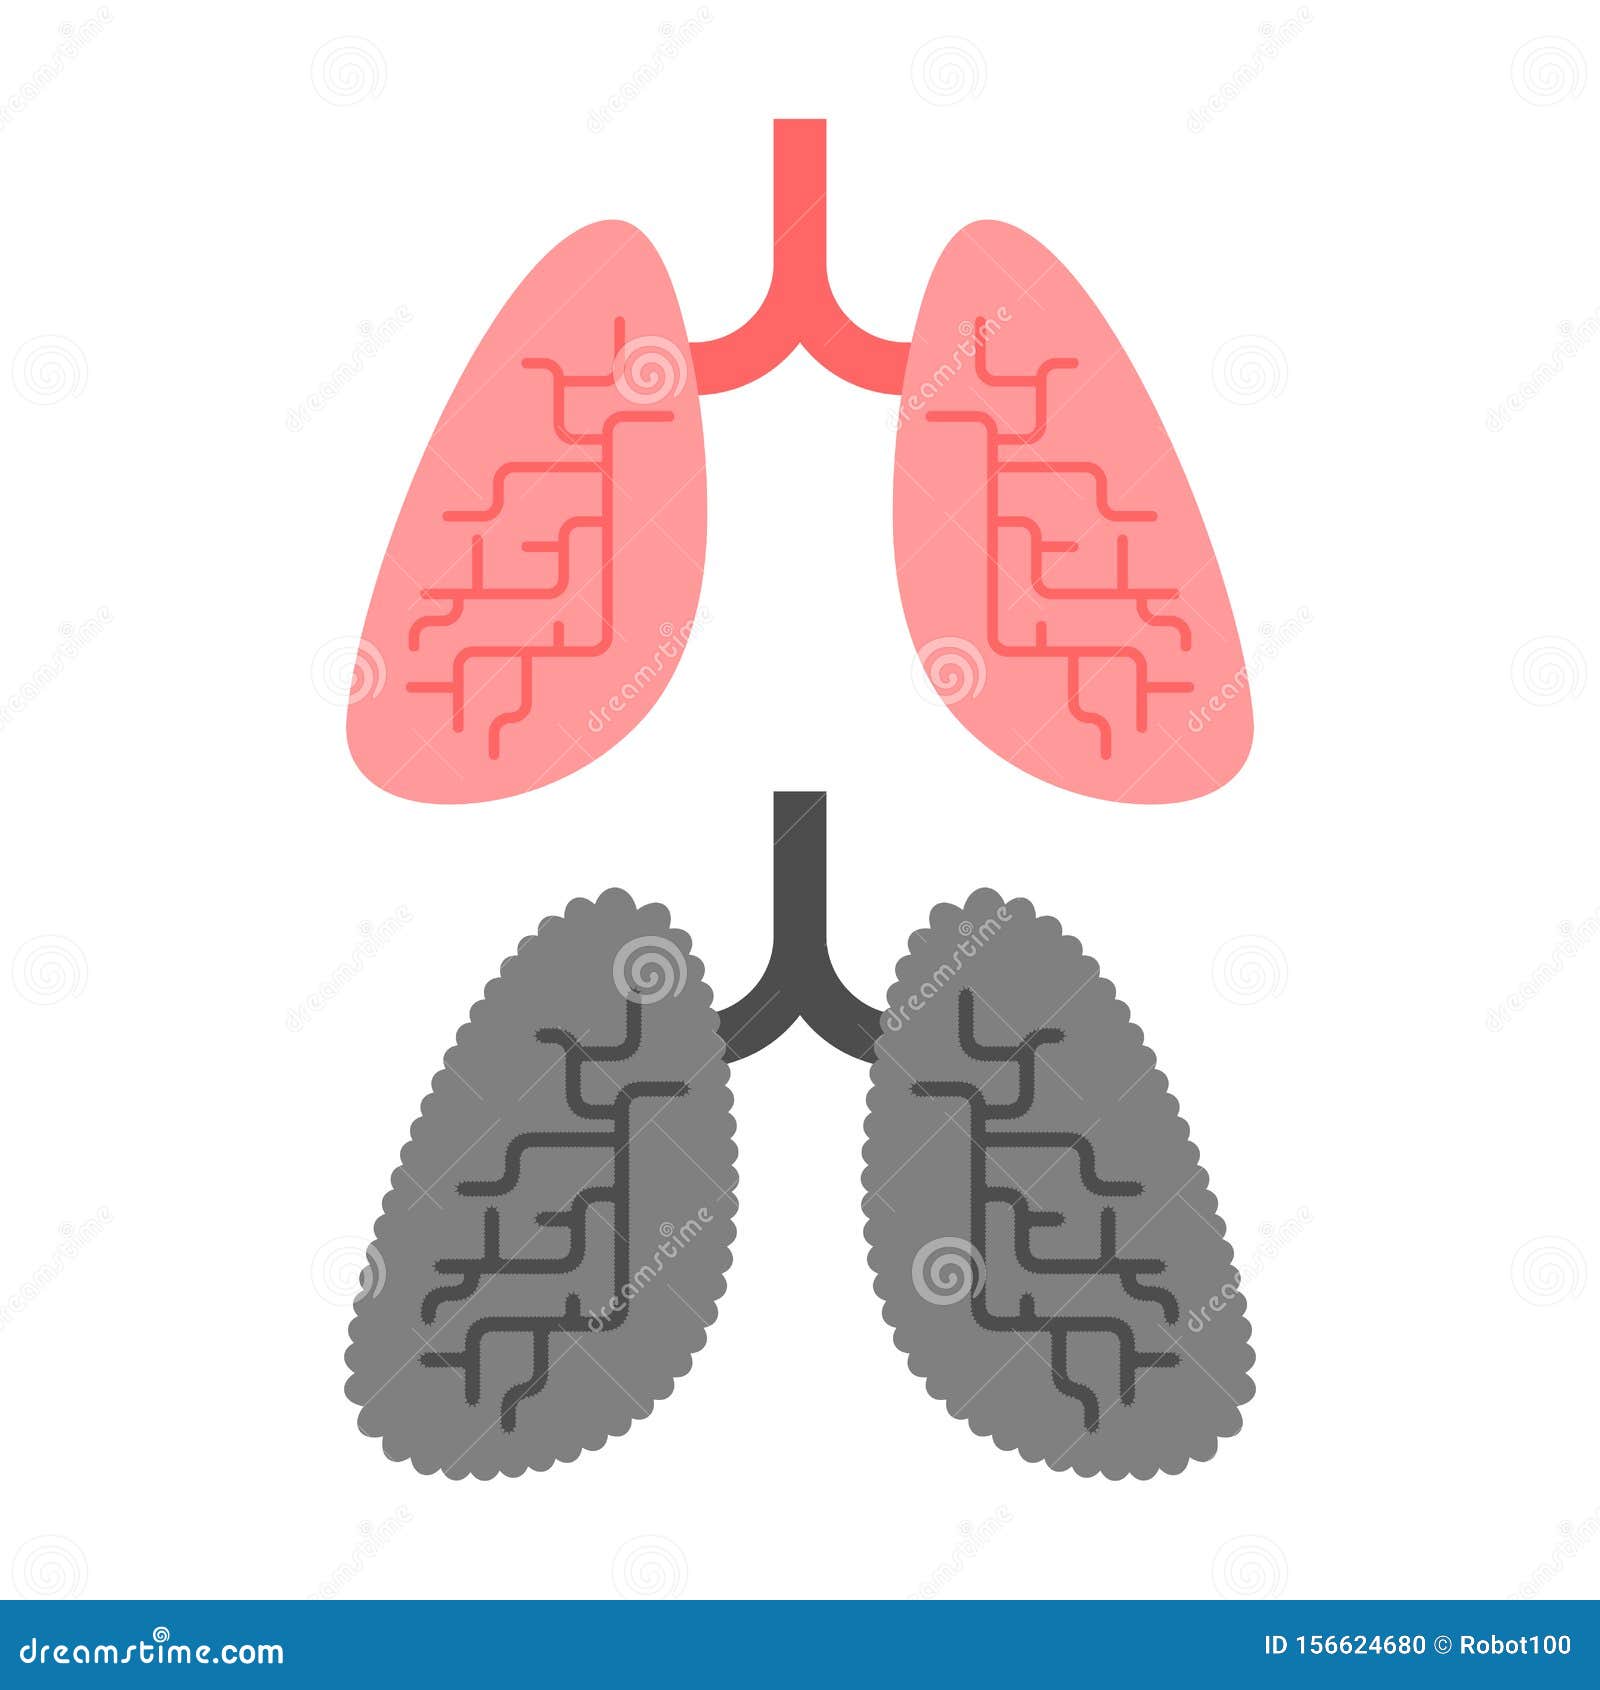

Здоровые Легкие Картинки

Здоровые Легкие Картинки 117 фото